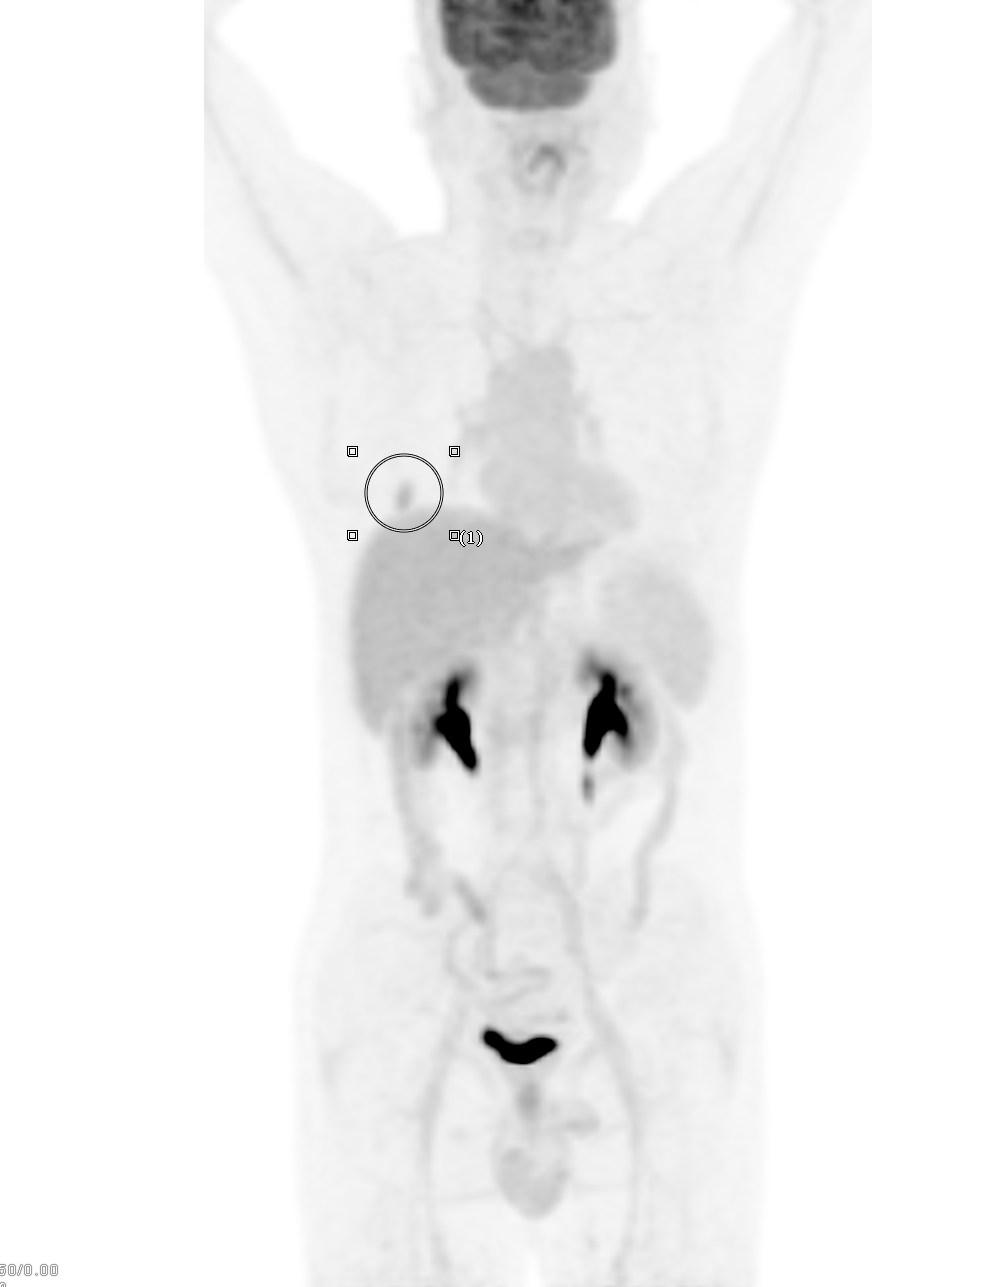

患者1:图4

全身PET/CT检查其他部位未见明显异常放射性浓聚灶,即全身其他部位未发现肿瘤性病变(未见明确转移)。不幸中的万幸,患者没有转移。通过检查可以进行一个肿瘤分期:T1cN0M0 属于ⅠA3期。这一类也算早期肺癌,术后治愈率不错。